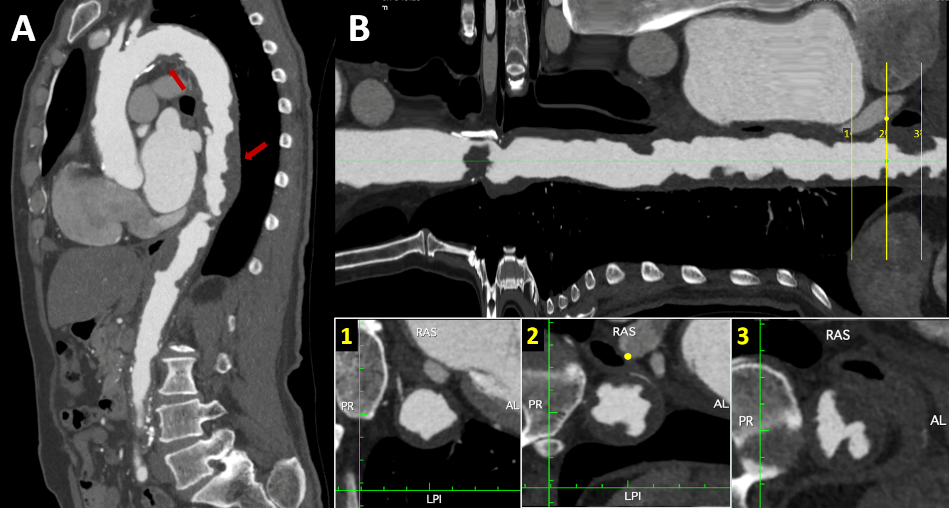

Figure 4

A. CT angiogram - Sagittal section of the aorta. Multiple atheromatous plaques, in tandem, along the entire course of the aortic arch and thoracoabdominal aorta (red arrows), predominantly in the supradiaphragmatic portion. B. Longitudinal reconstruction of the aorta. The cross section shows plaques with low attenuation coefficient (35 HU), irregular borders (lower central box), ulcerated and associated with images suggestive of thrombus (lower right box).

AL: anterior and left; CT: computed tomography; HU: Hounsfield units;; LPI: left posterior and inferior; PR: posterior and right; RAS: right anterior and superior.